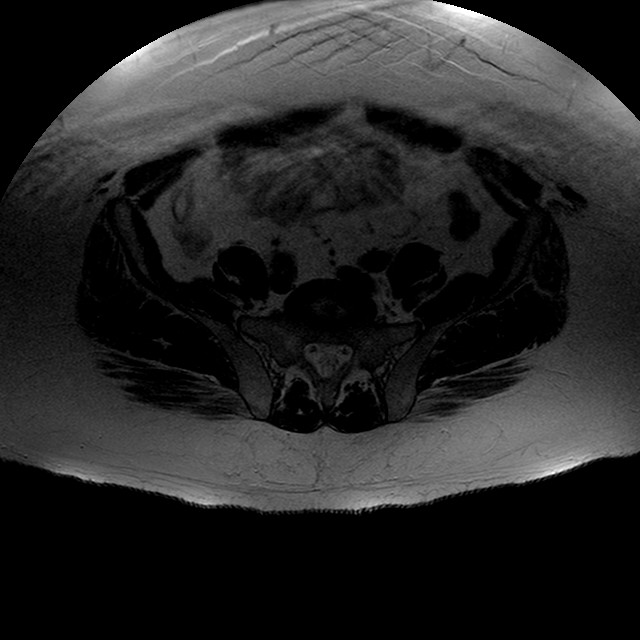

Esami: RMN BACINO

T2w TSE

Evidenti e simmetriche alterazioni osteofitosiche in regione coxo femorale con riduzione delle rime articolari. Degenerazione completa del cercine glenoideo. Non attuali segni di versamento articolare. Non segni di edema osseo che escludono attuale algodistrofia od osteonecrosi. Lieve e simmetrica riduzione del trofismo della muscolatura glutea.